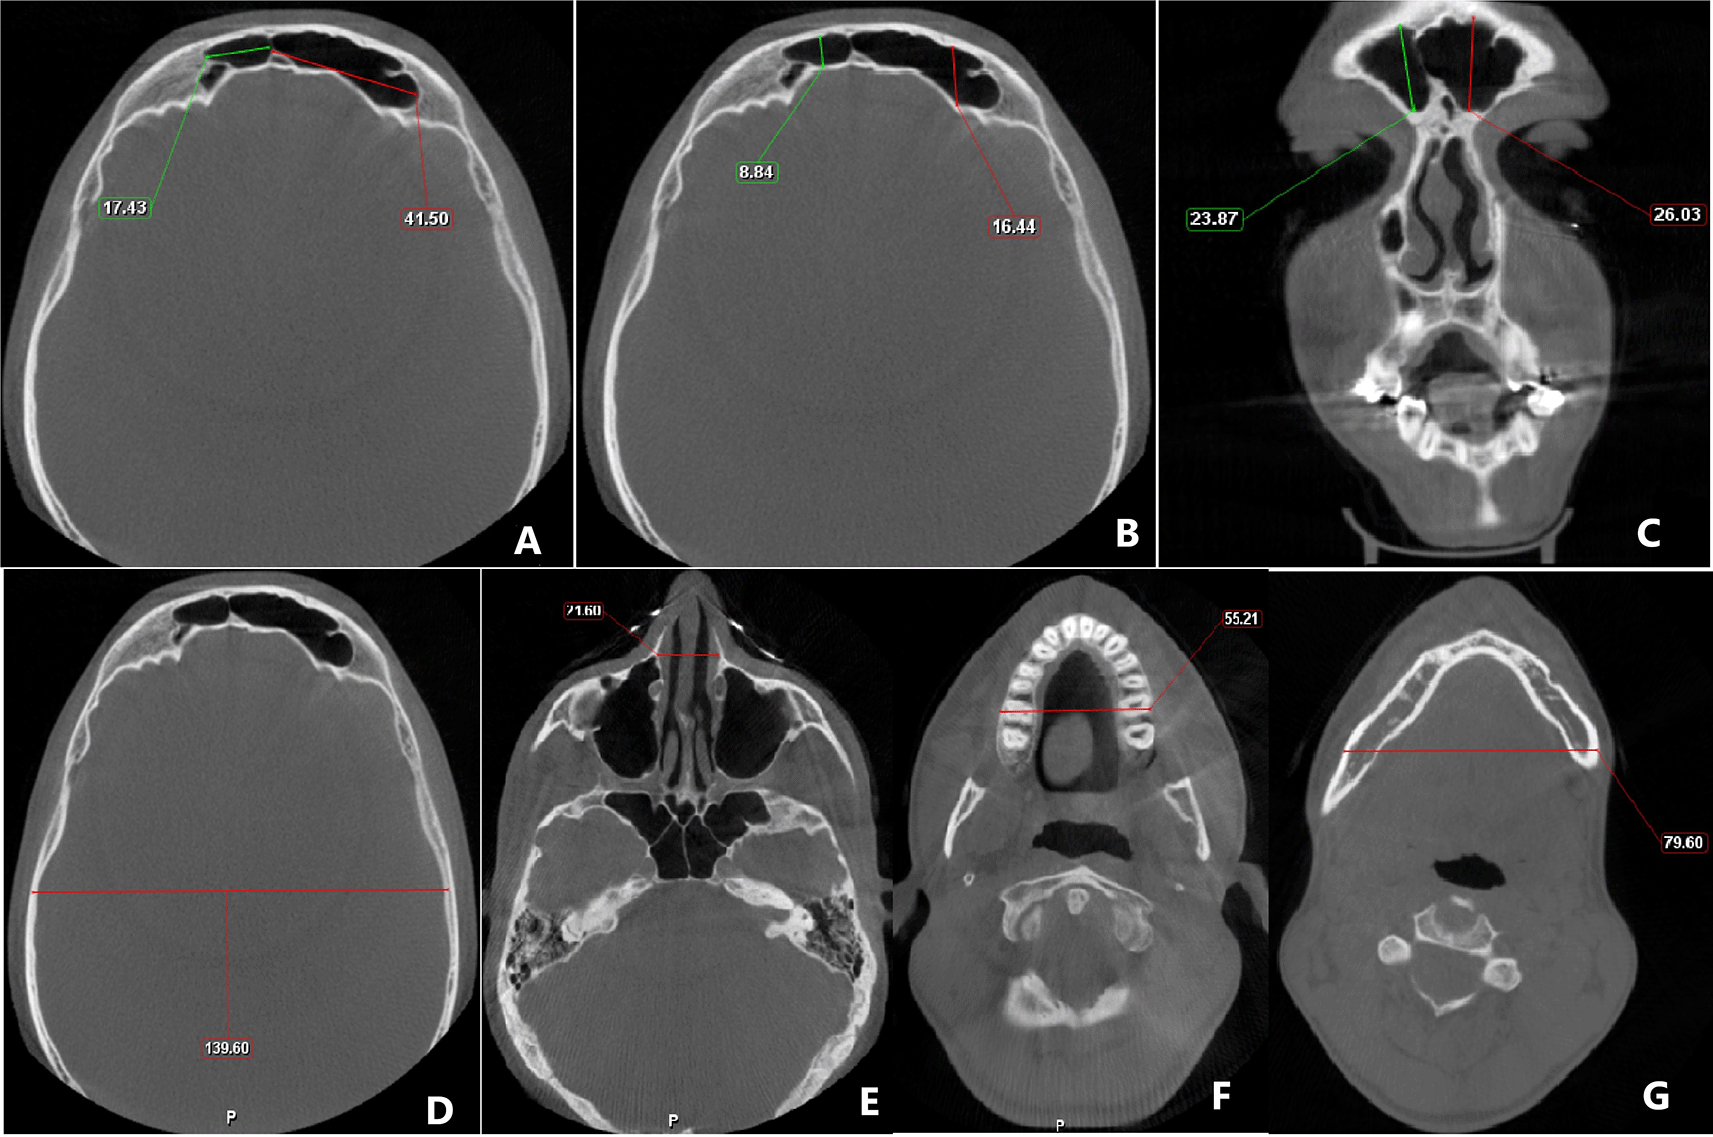

The linear measurements were done on the reconstructed image in the following way (Figure 1):

• Frontal sinus - For assessment of maximum supero-inferior measurements, the coronal section was utilized and measurement was taken between the highest and lowest point of both the right and left frontal sinus, while the axial section was used to measure the maximum antero-posterior and mesiodistal width of the left and right frontal sinus.

• Cranium - For the measurement of the maximum width of the cranium, the axial section was adjusted to the level of the superior border of the orbit (while looking at the coronal view), and at this level, measurement was taken from the inner cortical plate on one side to the inner cortical plate on the contralateral side.

• Nasal - The maximal nasal width was taken in the axial section after adjusting it at the level of the zygomatic arch.

• Maxilla - Axial section was skimmed till the maximal width of the maxilla was observed and in this section, measurement was taken.

• Mandibular width at antegonial notch - The maximum width of the mandible was taken at the level of the antegonial notch. For this purpose, first, the axial view was angulated so that in the sagittal section, the gonial and antegonial notch were observed. The axial view was then adjusted to the level of the antegonial notch and in this section, the maximal mandibular width was taken.

Figure 1. Cone-beam computed tomography image showing the measurements of A) mesio-distal dimension of frontal sinus; B) antero-posterior measurement of frontal sinus; C) supero-inferior measurement of frontal sinus; D) cranial width; E) nasal width; F) maxillary width; G) mandibular width.